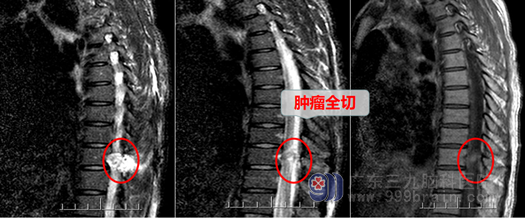

神经外科主任欧阳辉教授看到病人后详细的评估的吴女士的情况:肿瘤已压迫到神经,下肢功能、感觉已逐渐减退,再进一步发展就会出现脊髓横贯性损害:下肢就会瘫痪,大小便不能控制。所以手术治疗刻不容缓。为了将手术损伤降到最低,尽最大的可能保护功能,医生团队决定采用微创手术:即在一个微小的套筒内,在显微镜放大下全部切除肿瘤。由于肿瘤向椎管内已压迫脊髓,经过椎间孔已凸向胸腔,故这种手术也存在损伤脊髓、神经,甚至撕破胸膜,导致气胸的危险。主管医生邓心情与家属进行了耐心、细致的解释、沟通后,家属决定同意医生方案进行手术。在完善相关检查后,吴女士被安排在全麻下行“T10-11段椎管椎间孔内外肿瘤微创切除术”。手术进行得非常成功,肿瘤被完全切除,而脊髓、神经、胸膜都得到了完好的保护,没有被损伤。术后第二天吴女士的腿都可以抬起来了,明显比术前好很多,感觉也恢复了,术后第五天,在医生和护士的帮助下已可以下床走路了,也没有出现任何的大小便功能障碍。

吴女士及其家人高兴地说:微创手术就是好!外十科水平就是高!